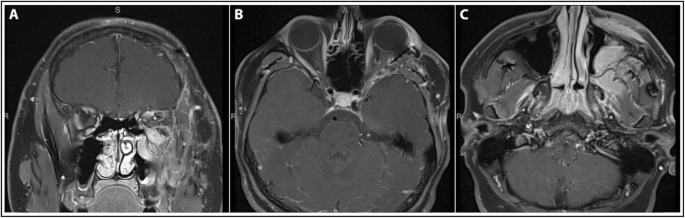

Following extracranial debulking, there was persistent multi-directional diplopia; however, MRIs obtained at approximately 1 month (Fig. 2c) and 4 month (Fig. 4) follow-up showed interval decrease in lesion size consistent with surgical resection, and stabilization of disease thereafter, including resolution of proptosis. Post-surgical cicatricial ectropion of the left lower eyelid along with myogenic ptosis of the left upper eyelid were subsequently repaired by oculoplastic surgery. No further treatment was required.

Follow-up MRI brain and orbits after second surgical debulking. Follow-up T1-weighted post-contrast MRI brain and orbits obtained approximately 4 months after second surgical debulking showing stable residual disease in the superior left maxillary sinus and along the left orbital floor involving the inferior rectus muscle in the (a) coronal plane, (b) axial plane at the level of the optic nerve, and (c) axial plane at the level of the maxillary sinus. Notably, the globes are normal in contour and there is resolution of prior proptosis